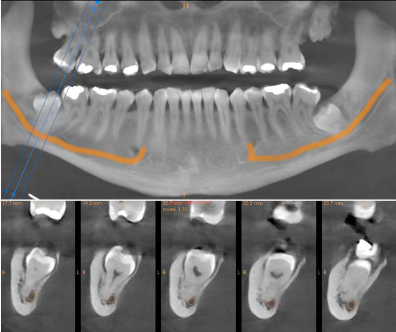

A CBCT scan was acquired using the Carestream CS 8200 to determine the exact 3D relationship between the impacted roots and the IAN canals. The difference between the panoramic view and the CBCT was immediate and clinically decisive.

Cross-sectional views of both sides showed the precise spatial relationship that the panoramic could only hint at. On the right side (LR8), the CBCT confirmed direct contact between the root and the nerve canal. On the left (LL8), the tooth was in close proximity but not in direct contact — a distinction that significantly affects the surgical approach and the informed consent conversation.

Reconstructed panoramic and cross-sections of tooth 48 showing root contact with the mandibular nerve canal Reconstructed panoramic and cross-sections of tooth 38 showing proximity to the mandibular nerve canal

Fig. 2 & 3 Left: cross-sectional views of LR8 (48) confirming direct root contact with the IAN canal. Right: cross-sections of LL8 (38) showing close proximity but no direct contact. This distinction — impossible to make on the panoramic alone — directly affects the surgical risk profile and the consent discussion.